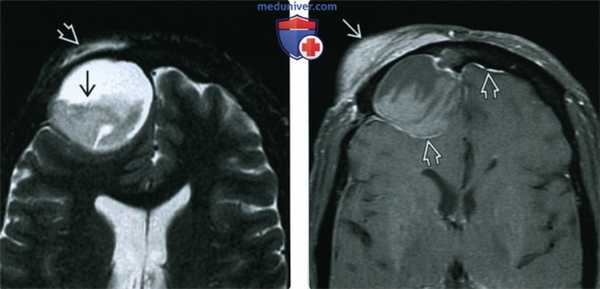

(Слева) При аксиальной МРТ Т2 FS визуализируется большое мукоцеле правой лобной пазухи с содержимым вариабельной интенсивности в нижних отделах. Мукоцеле распространяется в поверхностные мягкие ткани, приводя к их отеку.

(Справа) При аксиальной МРТ Т1 C+ FS у пациента с лобным мукоцеле: определяется отек и контрастное усиление поверхностных мягких тканей над разорвавшимся мукоцеле. Определяется также дуральное контрастирование передней черепной ямки, сопоставимое с ранним воспалением оболочек мозга.

(Слева) На аксиальной МРТ (Т2 ВИ FS) определяется большое мукоцеле правой лобной пазухи с уровнем «жидкость-жидкость» и компонентами с различной интенсивноаью сигнала. Мукоцеле распрсктраняется в поверхностные мягкие ткани, приводя к отеку.

(Справа) На аксиальной MPT (Т1 ВИ FS) у этого же пациента определяется отек и контрааное усиление поверхностных мягких тканей над разорвавшимся мукоцеле. Контрастирование твердой мозговой оболочки в передней черепной ямке сопоставимо с ранними воспалительными изменениями.